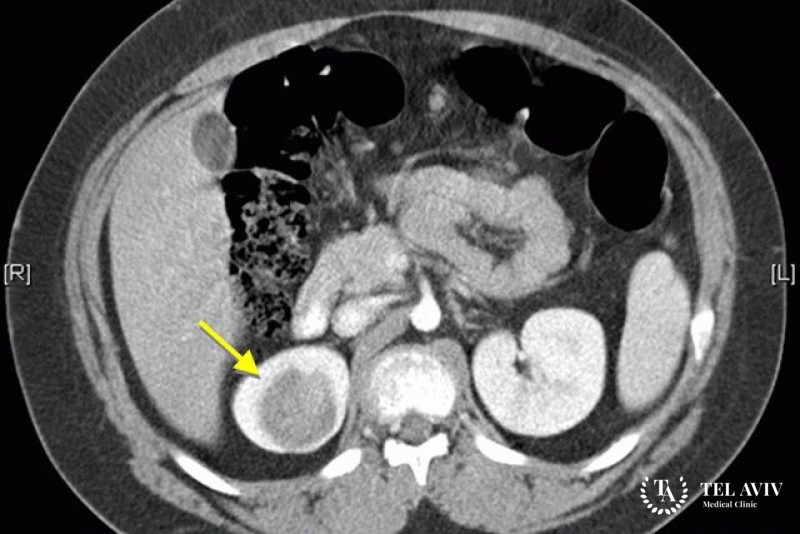

Нефробласто́ма (опухоль Вильмса) – злокачественное образование, которое состоит из эмбриональных клеток. Данное заболевание встречается в 30% случаев у людей в возрасте до 20 лет. Патология зачастую выявляется, когда метастазы уже распространились по организму и вызвали патологические изменения. Поэтому так важно вовремя диагностировать заболевание и приступать к оперативному лечению. К сожалению, симптоматика заболевания не ярко выражена.

- УЗИ внутренних органов;